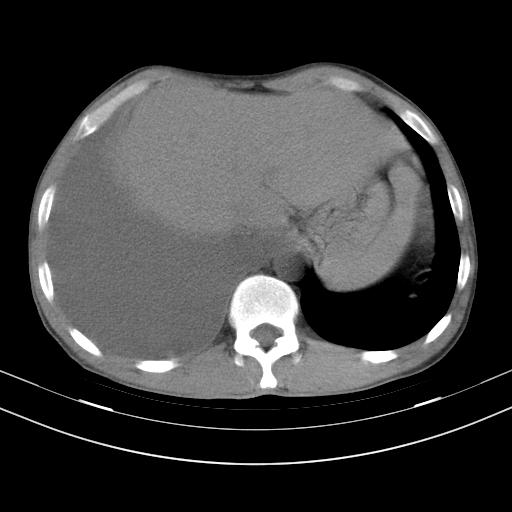

男性,44岁,结核病史多年。现胸闷气短,咳嗽,偶咳血。

右侧胸腔积液

右肺下叶不张

双肺多发结节影最分空洞形成考虑占位不除外结核

双肺陈旧性病变

1、右侧大量胸腔积液伴右肺压缩性膨胀不全,建议抽液治疗后复查 2、两肺继发性tb伴空洞形成。

1)两肺继发性肺结核伴空洞形成,左肺多发性结核球。2)右侧大量胸腔积液伴右肺部分膨胀不全。3)纵隔淋巴结肿大。

吉大一院胸水抽检结果:结核性胸水